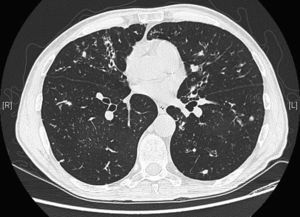

We report the case of a 64-year-old man, health worker, with no significant personal history or known toxic habits, who reported a 3-year history of non-productive cough, with no particular diurnal pattern, dysphonia and excess mucosity in the oropharyneal cavity, and additionally, in the last year, asthenia and recurrent episodes of low-grade fever. Forced spirometry results were as follows: FEV1/FVC 0.46; FEV1 1.91L (60%); FVC 4.14L (101%). Bronchodilator challenge and skin prick tests with allergens were negative. Computed tomography of paranasal sinuses, sweat chloride test, IgG, IgM, IgA, IgE and alpha-1 antitrypsin levels were all within normal ranges. A human immunodeficiency virus test was negative. A barium swallow study of gastroesophageal transit revealed gastric reflux. Chest CT showed bronchiectasis in the middle lobe and lingula associated with mucus plugs and distal centrilobular nodes (Fig. 1). Macroscopic results from fiberoptic bronchoscopy sampling were normal, while M. avium complex was isolated from bronchoalveolar lavage. The patient met diagnostic criteria for environmental mycobacteria published by the American Thoracic Society (2007)3 and was diagnosed as having MAC infection consistent with LWS.